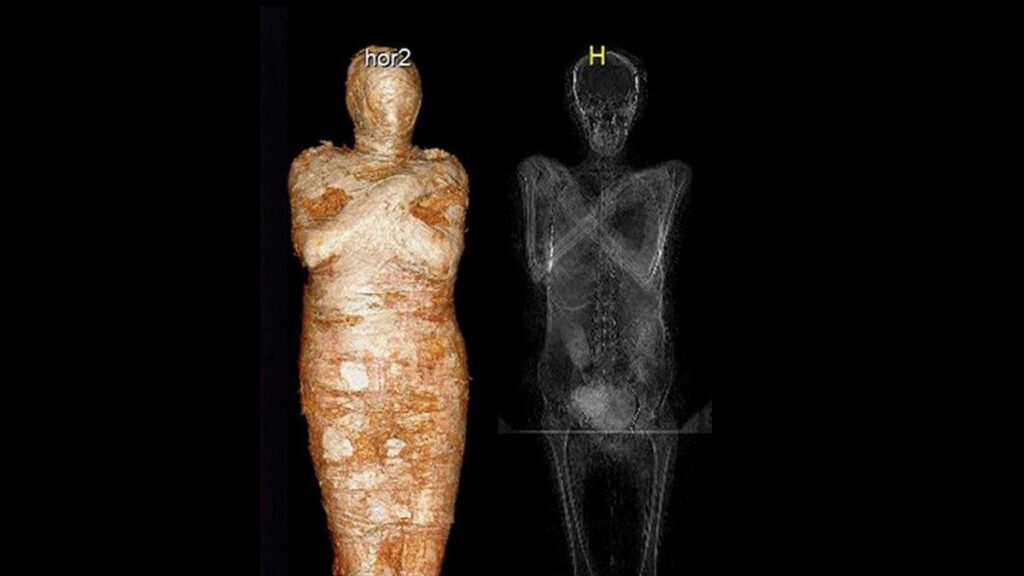

Científicos reconstruyen rostro de momia

México 18 noviembre._ Con tecnología de reconstrucción facial digital sobre restos humanos se reconstruyó el rostro de una momia egipcia muy especial. Se trata de la primera momia embarazada del mundo. Corresponde a una mujer que murió de cáncer hace 2.000 años. Los científicos hallaron restos de un feto en la matriz de la momia, […]